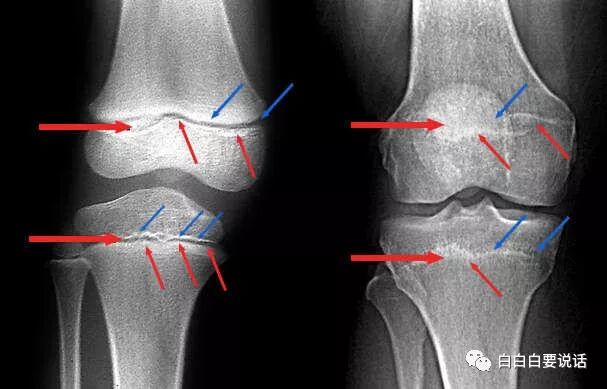

先认识下骨垢线(最重要)

这两张是膝关节的x线正位片,左边红蓝箭头标出来的两道缝不是骨折,是骨骺线,别以为它是两道缝,里面是一层充满干细胞的软骨,骨头就是从这里一点一点长出来的。

右边那个膝盖骨骨骺线消失了,木有了,那就是闭合了。。

如果骨骺线已经闭合,自然长高你就别想了,不要傻乎乎的送过去让别人宰了(被骗钱)。